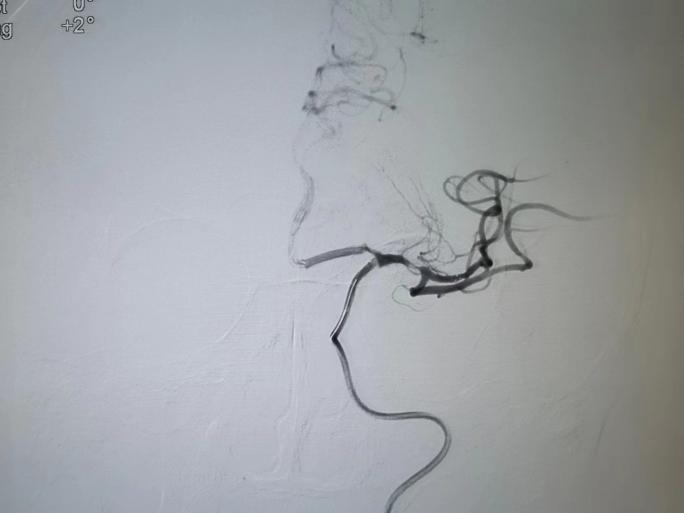

造影左侧大脑中动脉未显

4号早上8点半,呼叫铃又响起。家人发现徐大爷再次出现嗜睡等症状,情况危急,郭春晖主任判断徐大爷的血管出现了再发闭塞。头颅MRI+MRA显示徐大爷侧脑室旁脑白质变性,脑萎缩;颅内动脉粥样硬化,局部管腔狭细;左大脑中动脉闭塞,两侧胚胎型大脑后动脉。

取栓后M1段局部重度狭窄,血流速度减慢

球囊扩张治疗后脑中动脉M1

及以远段分支血流较前改善